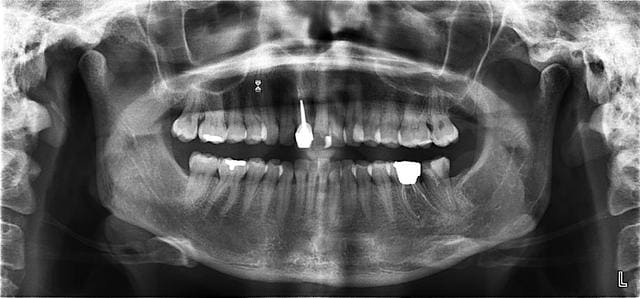

La pano montre une bonne cicatrisation des LPA avec reformation de la lamina dura autour des apex de 36-37. Les dents de 31 à 35 sont saines. 38 absente depuis longtemps.

Le nerf mandibulaire passe à distance des apex des dents (1 cm environ).

J'ai retrouvé la pano avant les soins qui date de juillet 2008. j'essaye de scanner la deuxième.